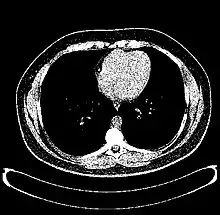

The Hounsfield scale (/ˈhaʊnzfiːld/ HOWNZ-feeld), named after Sir Godfrey Hounsfield, is a quantitative scale for describing radiodensity. It is frequently used in CT scans, where its value is also termed CT number.

| Parenchyma | Lung | −700 to −600[22] |

| Liver | 60 ± 6[23] | |